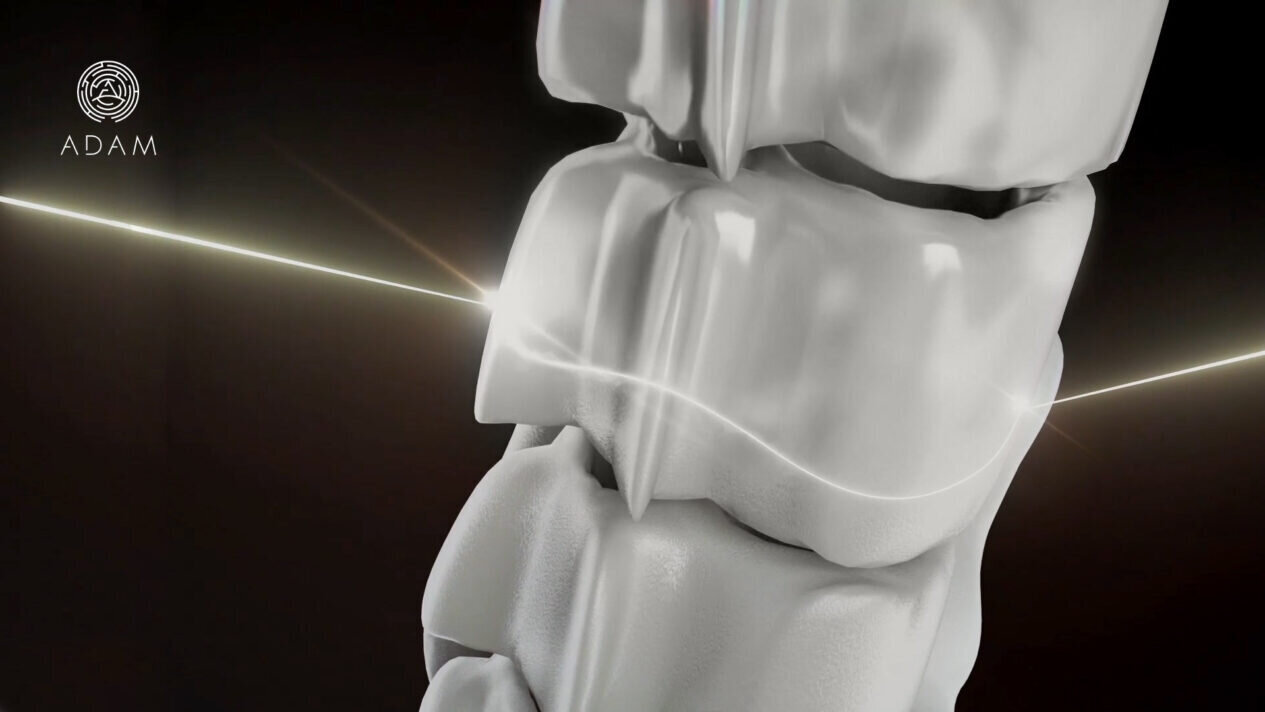

Making leaps in bone transplants

Image courtesy of ADAM Project

Designer: ADAM Project

Description: ADAM Project, a member of BioCT, was given clearance to take its 3D-printed bones to clinical trials in the US. The start-up is piloting the use of ceramics and polymer in 3D-printed bone implants.